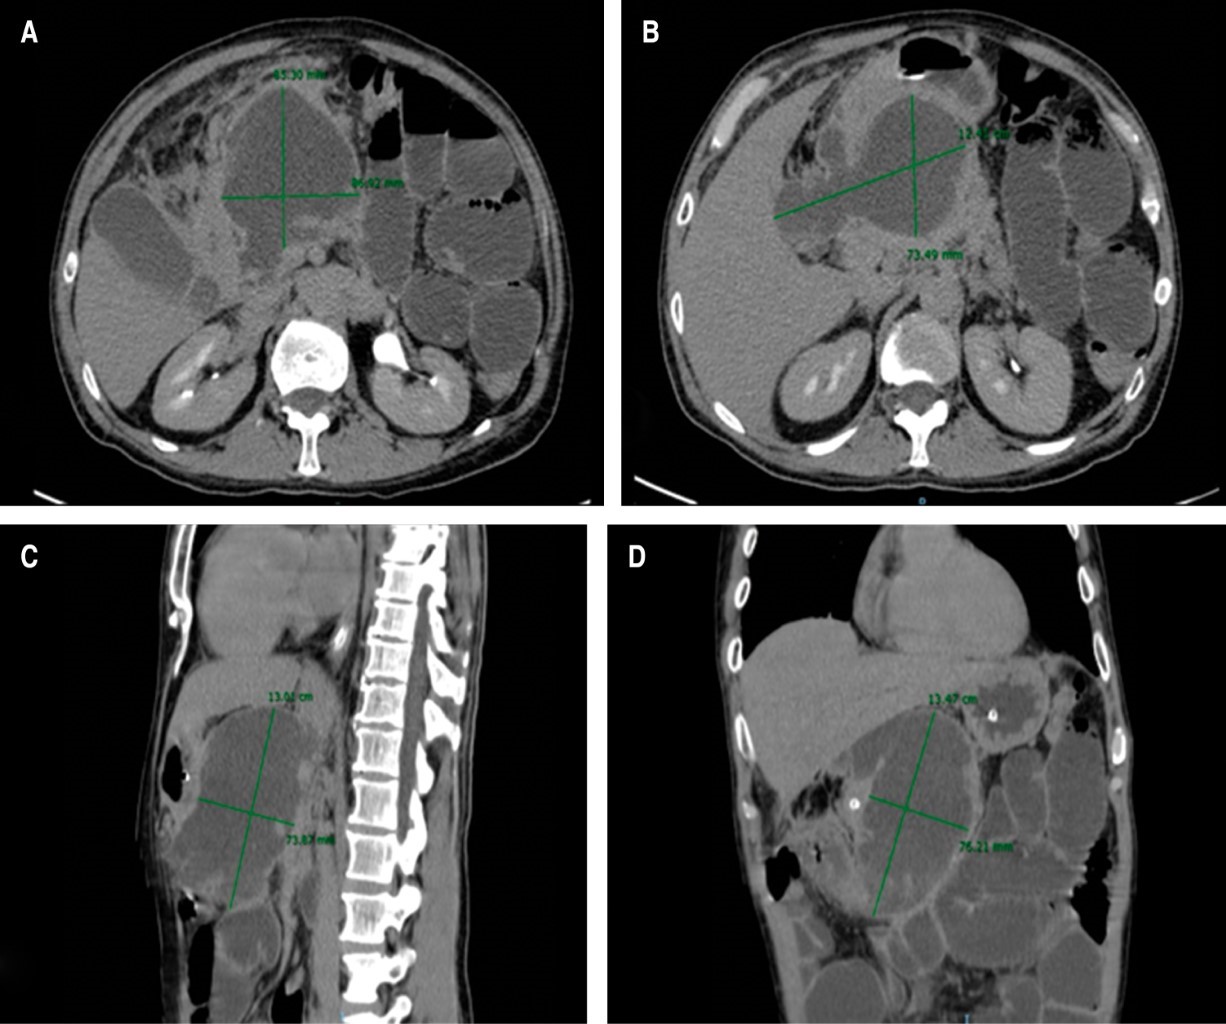

Paciente masculino de 48 años de edad con antecedentes de tabaquismo (IT 23), alcoholismo intenso, consumo de marihuana, hepatitis C, y antecedente de dos eventos de pancreatitis aguda leve de origen alcohólico resuelta sin aparentes complicaciones. Dos meses y medio después, acude por dolor abdominal al servicio de urgencias, presentando cuadro de hiporexia, náusea y vómito de dos días de evolución, encontrando a la exploración física dolor y aumento de volumen a la palpación a nivel epigástrico localizado a planos profundos, sin datos de irritación peritoneal, se completa el protocolo de diagnóstico documentando pancreatitis aguda alcohólica moderadamente severa. La tomografía axial computarizada (TAC) con evidencia de imagen hipodensa e irregular de 13.47 × 12.41 × 8.53 cm, pared definida y contenido heterogéneo correspondiente a un pseudoquiste pancreático de 746 ml de volumen (Figura 1). Se inicia con manejo de soporte hasta remisión de la pancreatitis aguda, posteriormente, se realiza derivación cistogástrica laparoendoscópica, con hallazgos de pseudoquiste pancreático de contenido necrótico septado, que desplaza estómago, obteniéndose un total de 700 ml de líquido turbio y detritus (Figura 2). Se coloca sonda nasoyeyunal de triple lumen para su alimentación enteral inmediata y descompresión gástrica. El paciente egresó en dos días del Servicio de Cirugía General del Centenario Hospital "Miguel Hidalgo" con sonda nasoyeyunal y control por consulta externa, la cual se retira tres semanas después del evento quirúrgico, tolerando adecuadamente la vía oral.

Figura 1